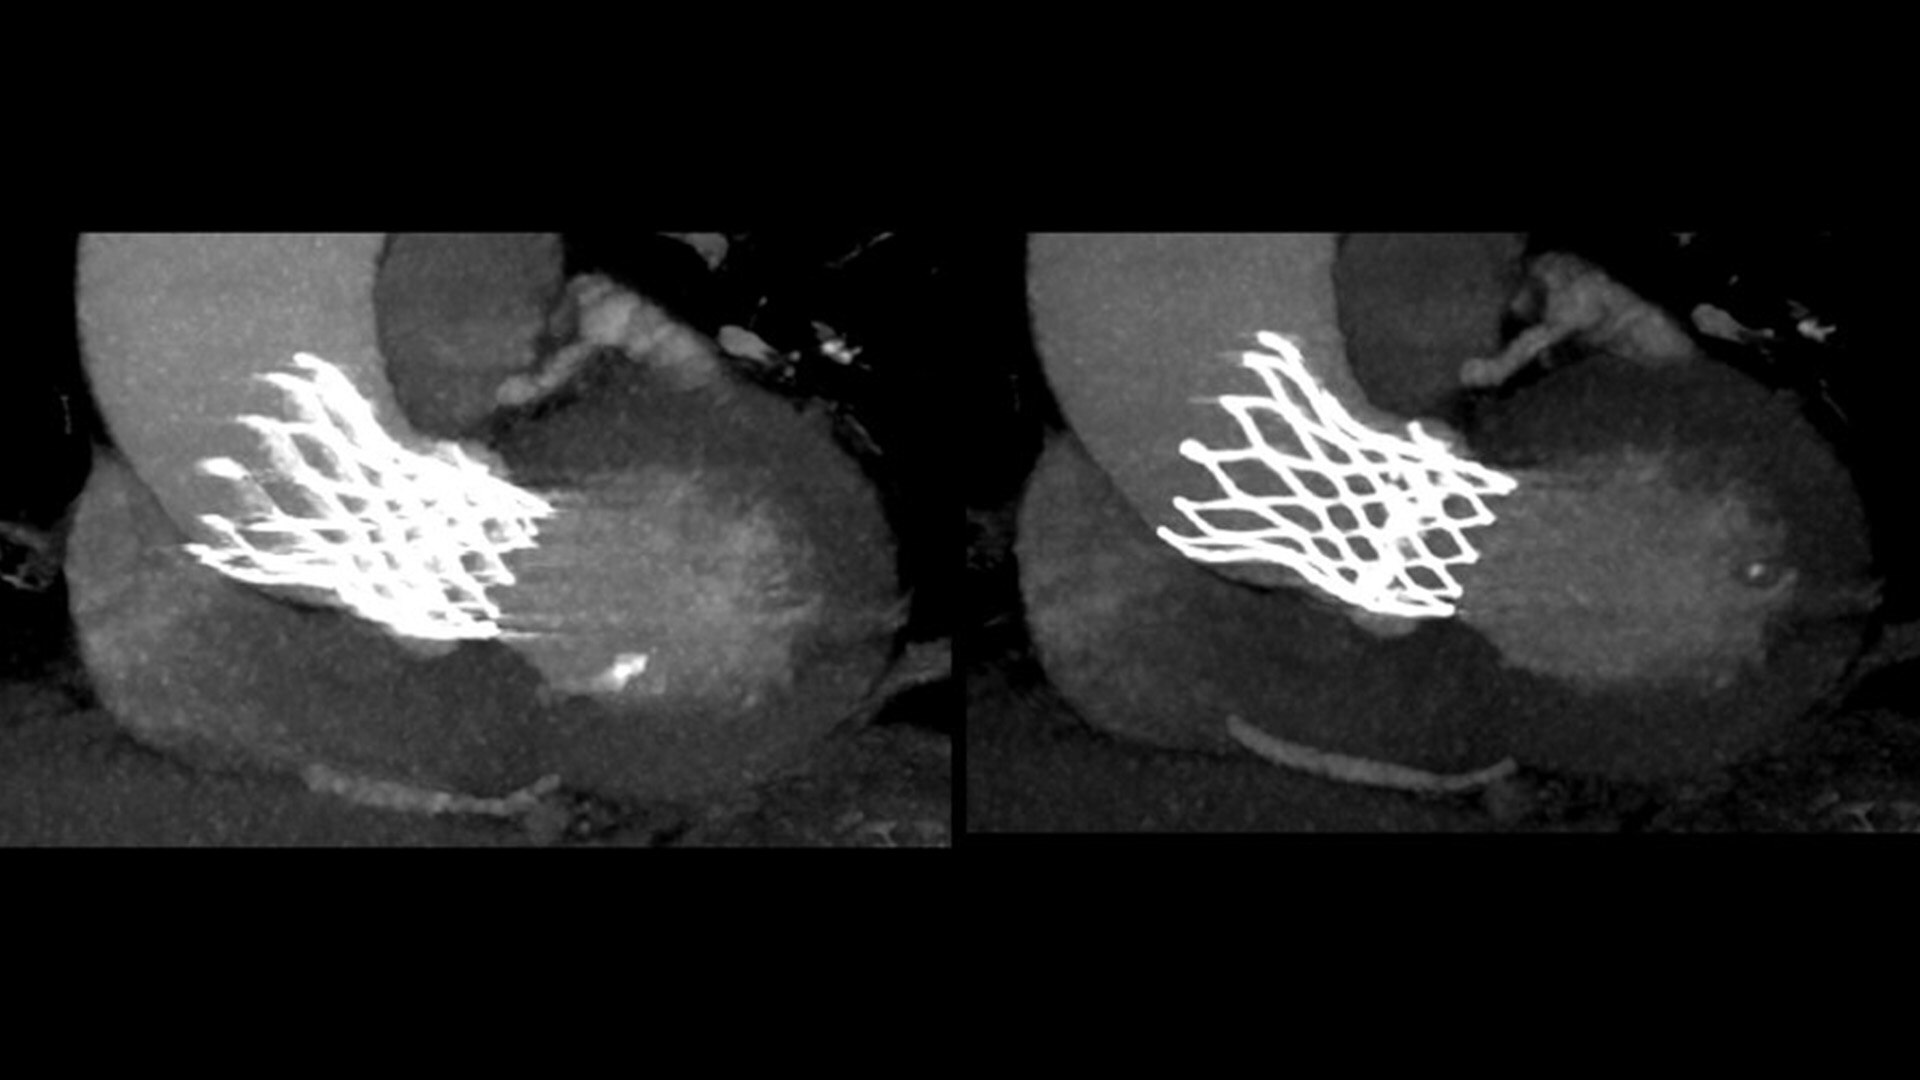

SnapShot Freeze 2

Intelligent and automated whole-heart motion correction for enhanced Cardiac CT imaging.

Motion correction

6x reduction in motion artifacts1

Temporal resolution

19.5 msec effective temporal resolution at 0.23s/rotation gantry speed2